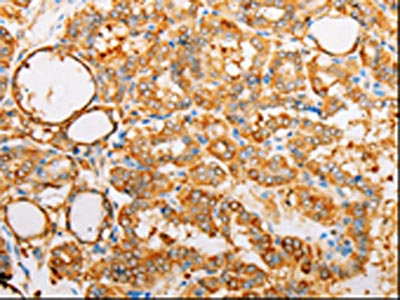

The image on the left is immunohistochemistry of paraffin-embedded Human thyroid cancer tissue using CSB-PA957575(ARF1 Antibody) at dilution 1/25, on the right is treated with synthetic peptide. (Original magnification: ×200)